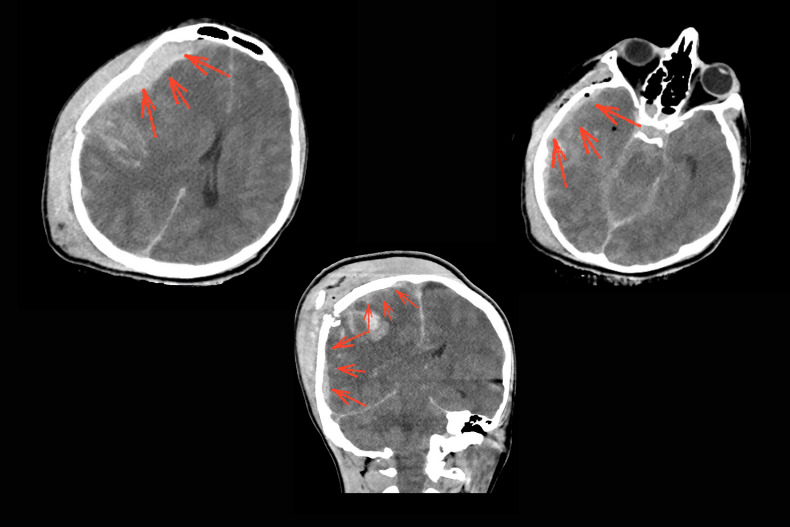

Malign MCA enfarktı çoğu zaman tek başına geniş bir beyin yarım küresini etkilerken, bazı olgularda tabloya ICA (Internal Carotid Artery) oklüzyonu da eşlik edebilir. ICA tıkanıklığında hem MCA hem de anterior serebral arter (ACA) sulama alanları etkilenebilir ve ortaya çıkan enfarkt alanı çok daha geniş olur. Bu durum BT’de yaygın hipodens alan, belirgin beyin ödemi, ciddi orta hat kayması (shift), ventrikül basısı ve bazal sisternlerin silinmesi ile kendini gösterir. Klinik olarak hızla bilinç bozulması gelişir ve beyin sapı herniasyonu riski artar.